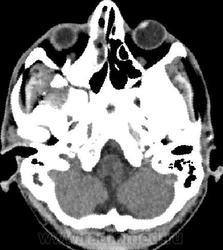

- тотальное снижение пневматизации обоих половин лобных пазух, обоих гайморовых пазух, передней и средней групп ячеек решетчатого лабиринта с двух сторон патологическим содержимым плотностью +17+23HU. Устья гайморовых пазух блокированы патологическим субстратом.

По задней стенке правой половины лобной пазухи определяется выбухание патологического содержимого в полость передней черепной ямки с наличием реактивного утолщения надкостницы ~на 5 мм. При контрастном усилении наблюдается интенсивное накопление контрастного вещества толстой стенкой отграниченного образования, содержимое пазух не накапливает контрастный препарат.

-определяются костные дефекты задней стеки правой половины лобной пазухи, определяется дефект перегородки, разделяющей половины лобной пазухи, дефект передней части костной стенки левой половины лобной пазухи. Дефект верхне-медиального отдела крыши правой орбиты.

Также определяется канал со склеротическим контуром, сообщающийся с полостью левой гайморовой пазухи и полостью рта, шириной 1,7 мм являющийся ороантральным свищом;

-признаки хронического остемиелита в виде неравномерного утолщения костных стенок (гиперостоз) обоих гайморовых пазух, обоих половин лобной пазухи, истончение и изъеденность стенок средней группы ячеек решетчатого лабиринта справа, изъеденность медиальной стенки орбиты (бумажная пластинка решетчатой кости) справа. Патологических изменений со стороны ретробульбарной клетчатки, содержимого орбиты достоверно не выявлено.

- определяется участок пониженной плотности в полюсно-базальных отделах правой лобной доли (+25+30Hu), являющийся зоной энцефалита, без четких контуров, не накапливающий контрастный препарат при контрастном усилении.

Заключение: КТ признаки полисинусита, осложненного хроническим остеомиелитом стенок гайморовых и обоих половин лобной пазухи, ячеек решетчатого лабиринта справа, наличием участков деструкции стенок обоих половин лобной пазухи, зоны энцефалита в полюсно-базальных отделах правой лобной доли. Полипы передне-верхней стенки левой половины основной пазухи, среднего носового хода справа. Признаки ороантрального свища слева.